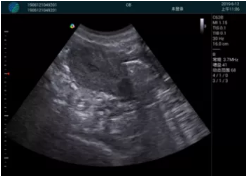

腺體內(nèi)部清晰顯示一低回聲塊影,形態(tài)不規(guī)則,邊界模糊,邊緣呈毛刺狀,內(nèi)部見(jiàn)砂礫樣鈣化

M20引導(dǎo)下穿刺活檢術(shù)

M20引導(dǎo)下平面內(nèi)穿刺取出的腫塊組織